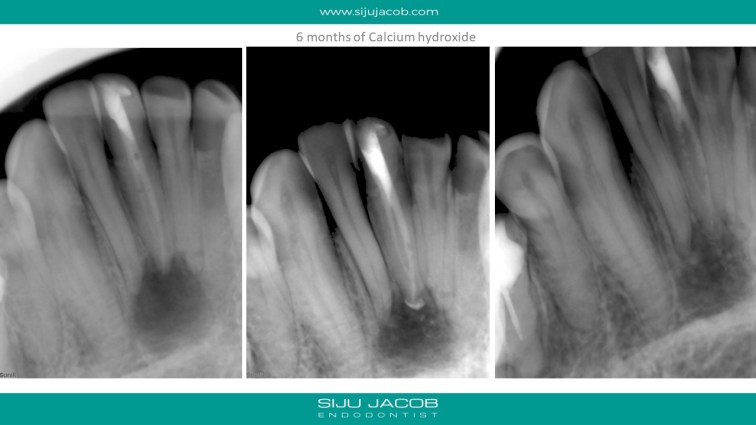

This patient had a lesion involving three teeth in the mandibular anterior region. He was seen by multiple clinicians and all of them had advised endo on 3 teeth followed by surgery. I treated just the one tooth which tested non-vital. I placed Long-term calcium hydroxide (6 months) to see some evidence of healing before obturation.